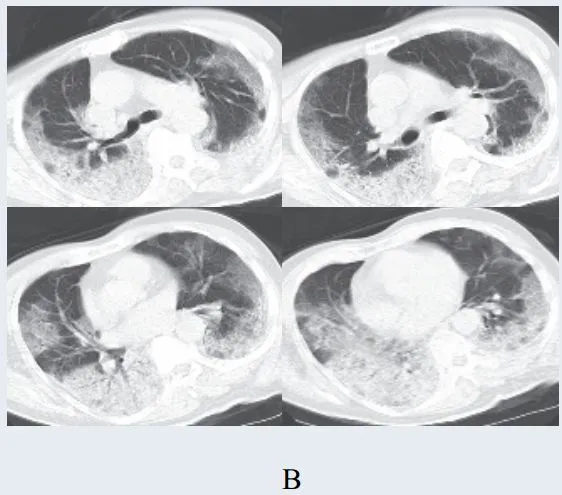

图2-1 早期病灶多数分布贴近胸膜(共4张)

绝大多数案例出现磨玻璃病灶,最低测得 CT 值约为-600Hu(图 2-3) ,病灶内血管穿行可清晰显示;部分案例磨玻璃病灶与实性病灶共存

根据既往严重急性呼吸综合征(SARS)病理学机制,提示此为肺泡间隔毛细血管扩张充血、肺泡腔内液体渗出和小叶间隔间质水肿

图 2-3 早期绝大多数病灶表现为磨玻璃密度(共4张 )